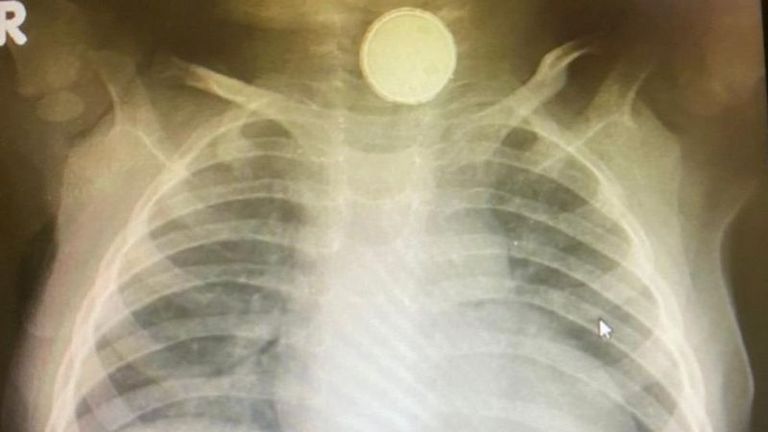

أظهرت فحوصات طبية أن بطارية ظلت عالقة في حلق رضيعة لمدة 4 أشهر، بعد أن اعتقد الأطباء أنها تعاني من التهاب اللوزتين.

وبعد أن كشفت صور الأشعة عن بطارية صغيرة عالقة في المريء، خضعت صوفيا جريس هيل لعملية جراحية استغرقت ساعتين لإزالة البطارية، وهي الآن تتغذى بالسوائل.

وبعد زيارة أخرى إلى المستشفى في مايو/أيار، كشفت الأشعة عن وجود بطارية في المريء سببت لها أضرارا بالغة لأنها كانت متآكلة.